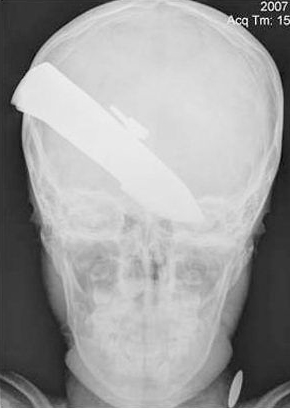

千钧一发之际,男孩为了掩护父亲挺身而出,却不幸被那把长达3英寸(约7.62厘米)的匕首由头颅右上方斜穿而入,直插左眼眼窝!令人吃惊的是,脑袋中刀后的男孩虽然血流如注,但却神志清楚,甚至可以自行行走。情急之下,男孩父亲带着儿子来到驻扎在坎大哈市的英军军营求助。

由于不清楚男孩颅内受伤情况,谁也不敢将深嵌其中的匕首贸然拔出。无奈之下,英军随后动用一架军用直升机将男孩送往位于坎大哈市附近堡垒军营的208野战医院抢救。当值的斯蒂芬·加拉切尔上校下令立即对受伤男孩进行X光检查。当斯蒂芬拿到X光照片时,不禁倒吸一口凉气。他回忆道:“当时那情景真够可怕的。如果之前有人将匕首强行拔出,势必导致一场灾难。因为谁也不清楚颅内的伤势究竟如何。”

最终,斯蒂芬在帐篷内为受伤的男孩进行了一场高风险的开颅手术,成功取出了那把3英寸长的“夺命匕首”。令人称奇的是,如今几个月过去了,男孩不仅顺利康复,而且几乎没有留下任何后遗症,就连视力也基本正常。